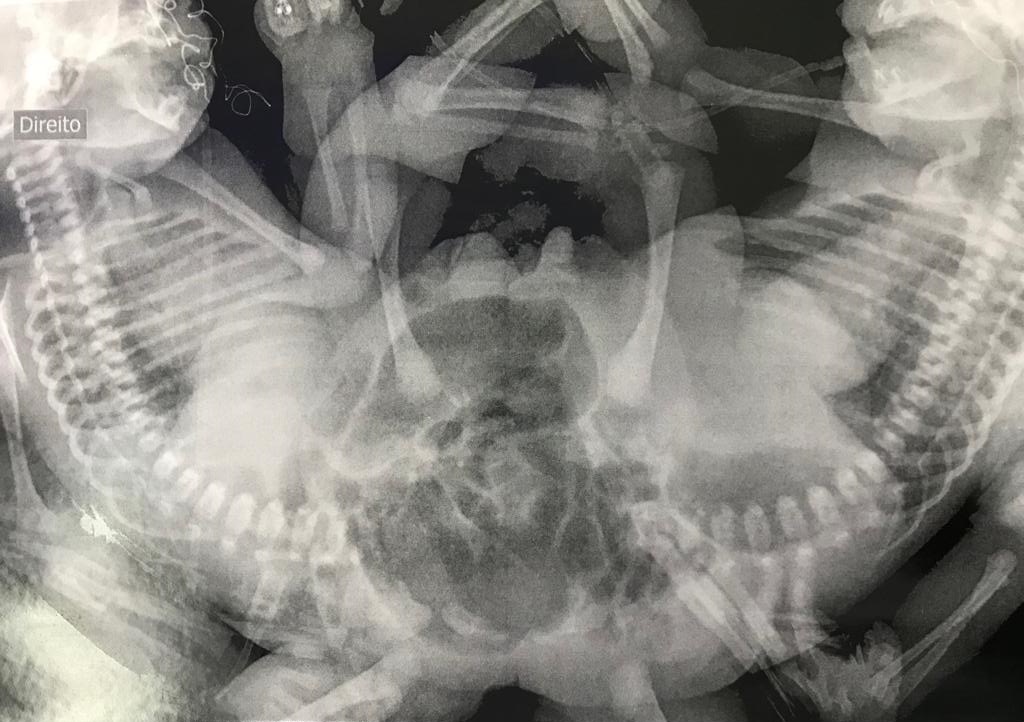

De acordo com o HMI, exames preliminares indicam que elas dividem o fígado e o intestino. Elas nasceram de 36 semanas e, juntas, pesam cerca de 3.798 kg. Internadas na Unidade de Cuidados Intermediários Neonatal (Ucin), o estado das duas é estável. Laura e Lais estão acompanhadas de uma tia.